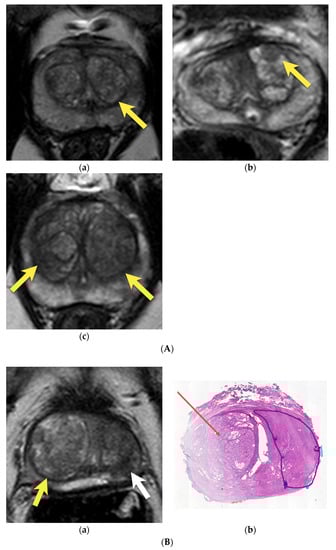

8. Post-Biopsy Hemorrhage

9. Prostatitis